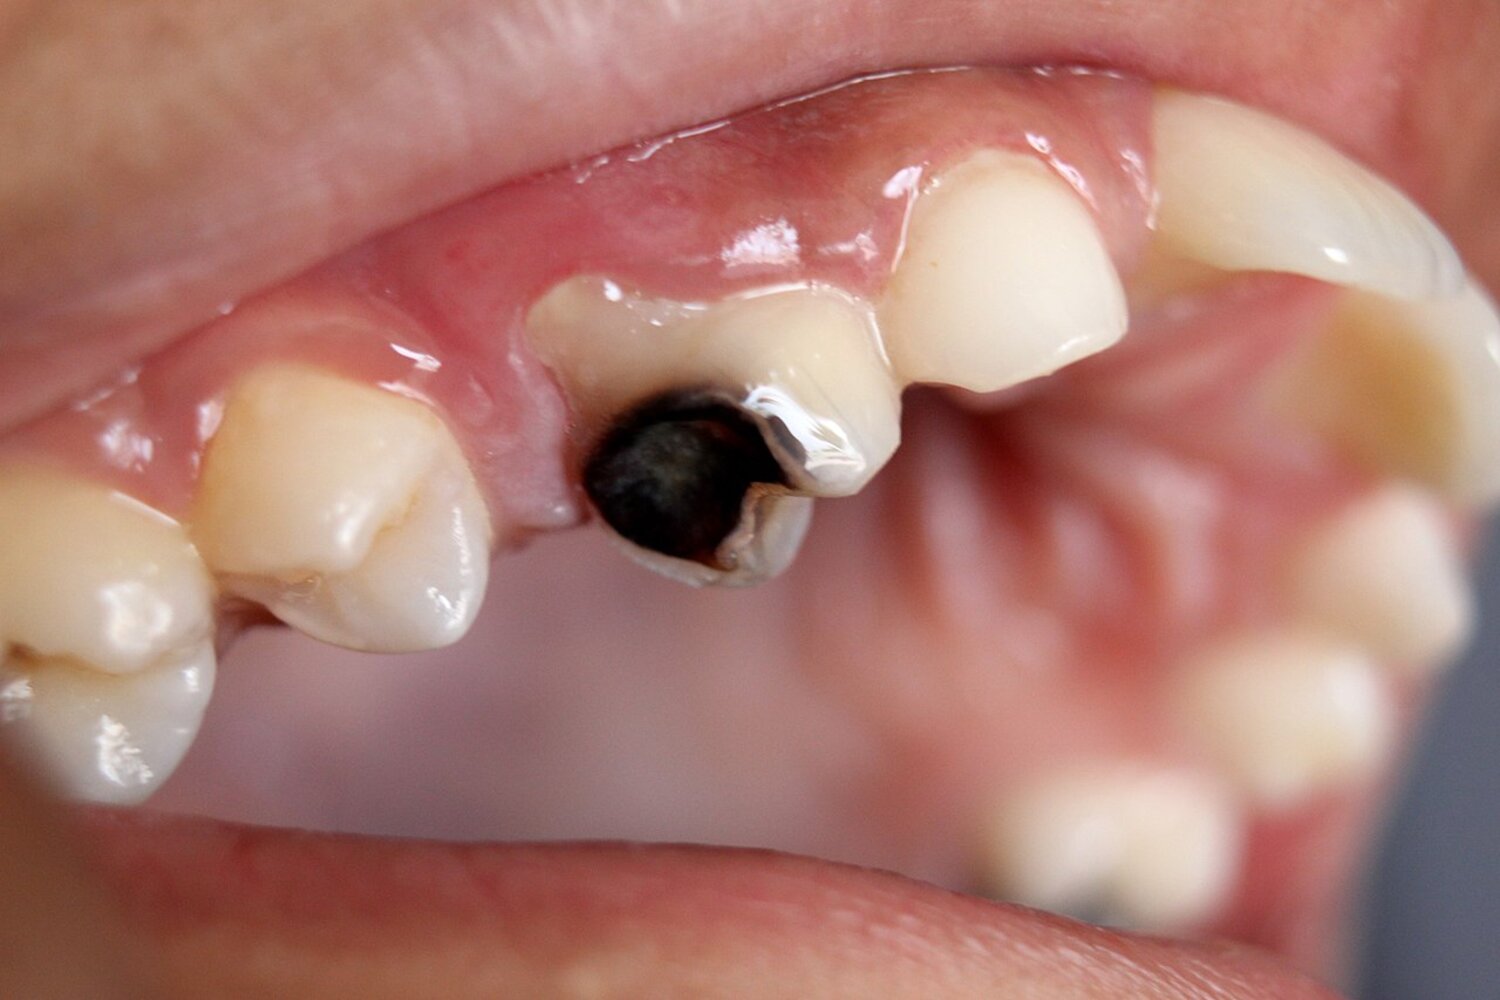

Overview

• Definition: the accumulation of purulent fluid within the dental pulp or periodontal tissue [10]

• Etiology [10]

• Dental caries

• Poor oral hygiene

• Trauma

• Unsuccessful root canal treatment

Clinical features

• Severe pain can generally be elicited with palpation.

• Swelling and erythema of the surrounding mucosa

• Purulent discharge from the gum line may be seen.

• The affected tooth may be discolored and/or show enamel breaks.

Management [8][9][10]

• Consult a dentist or oral surgeon for abscess incision and drainage, and, if necessary, removal of the affected tooth.

• Start empiric antibiotic treatment for systemic symptoms (e.g., fever) or if surgical intervention is delayed. [8][9][10][12]